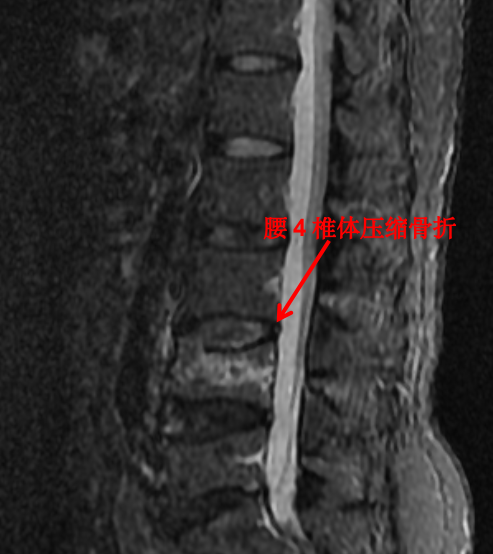

随着科技进步及医学的发展,核磁已经是脊柱外科不可或缺的检查手段。对脊柱、韧带、椎间盘、椎管内神经及椎旁组织显影都优于 CT,通过腰椎核磁我们可以直观地看到椎间盘突出的程度、神经受压的程度,以及压缩骨折的新鲜程度。

这对于脊柱疾病的治疗有着很重要的指导作用。优点是对脊柱及周围组织显影更清楚,无辐射。其缺点是价格昂贵,检查时间长,有幽闭恐惧症的患者难以接受。

前面提到的腰椎压缩骨折,X 光片可以看出楔形变,但无法判断新鲜骨折还是陈旧骨折,进一步完善腰椎 MRI 才能明确诊断,做出下一步治疗计划。